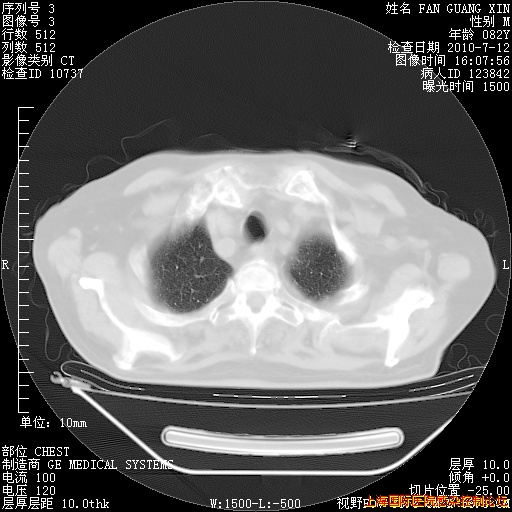

今天CT

整整相隔30天的肺部CT好像有所好转啊。甲强龙减量第3天,需要观察体温。

海管,自昨日你和我通完话后,不知您岳父消化道症状有无缓解?体温怎样?阅读7.12日胸部ct,个人认为目前激素治疗是有效的,甲强龙减量是适宜的。因在抗痨治疗,需密切观察肝功、肾功能和血常规。不过,老年、长期住院和大量使用激素,很担心菌群失调发生